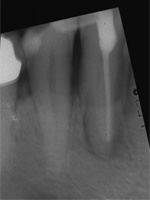

Dieser Zahn wurde schon geraume Zeit zuvor von einer Kollegin im Notdienst eröffnet und anschlies­send mit einer aufwendigen Amal­gamrestauration ästhetisch an­sprechend wieder verschlossen. (Bild 1) Uns blieb noch WK/WF, was bei massiver Überstopfung der hin­teren Wurzel auch gelang (Bild 2).

"Überstopfen ist immer noch besser als Unterstopfen" laut Koçkapan. OK, hier wurde des Guten aber ganz eindeutig zuviel getan.

Also direkt neben dem Zahn das Zahnfleisch ein wenig angehoben und zur Seite gedrängt und dann mit einem scharfen Löffel den Überschuss vollständig entfernt.

Schon 8 Monate später ist eine deutliche Verbesserung der Gesamt­situation unverkennbar (Bild 3). Verlorengegangene Knochensubstanz wurde in Teilen schon wieder aufge­baut, doch ist noch gar nichts entschieden. Schaun mer also ma'.

Abrechnungstechnisch hat der Mut zur WR an 38 gefehlt, deshalb nur EXZ1.